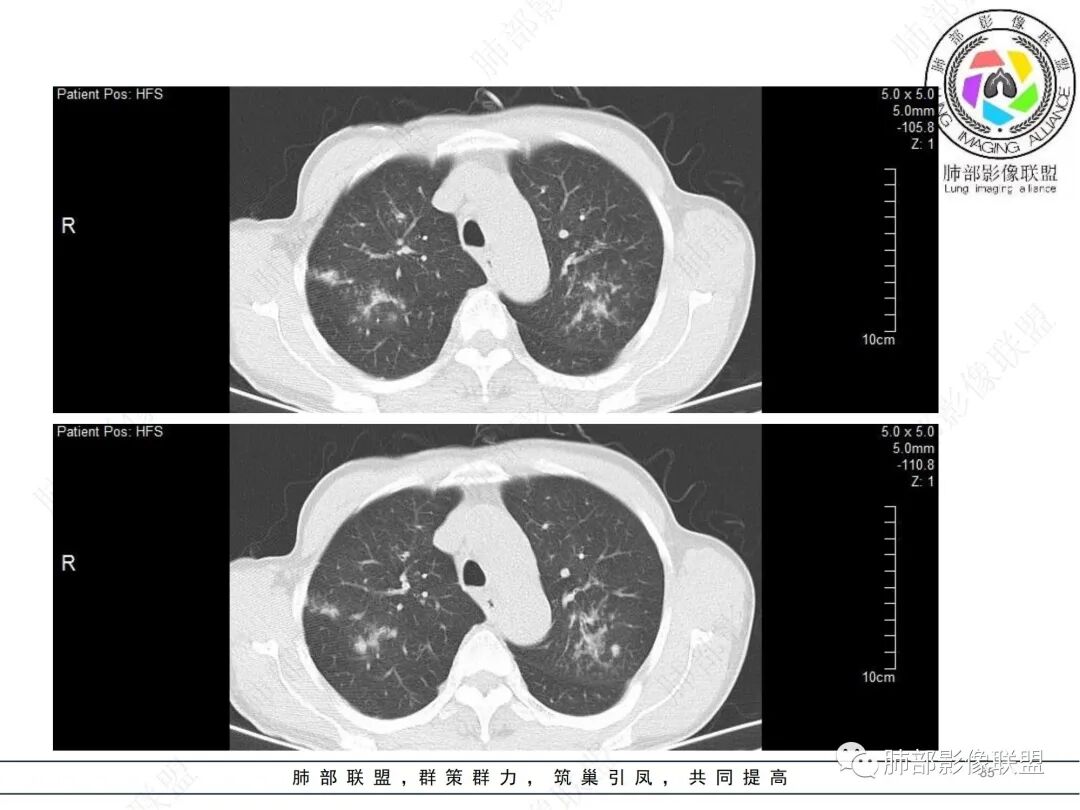

58岁男性,咳嗽胸闷3天,咳较多褐粘液痰,无发热。有2型糖尿病病史。白细胞与中性粒细胞升高。CRP升高。鳞状上皮细胞癌抗原轻度升高。结核T细胞免疫斑点实性阳性。肺炎支原体、衣原体IgG轻度升高。支气管镜显示支气管炎性改变、右肺下叶背段管腔狭窄。2.影像特点:

2022.6.24CT显示两肺弥漫性段、亚段支气管壁增厚(两肺各叶都累及),增厚的支气管壁外可见沿着支气管分布的渗出、实变影。另外远端肺内亦可见多发树芽影、结节影,其边界欠清晰。右肺下叶基底段局部胸膜下亦可见小斑片影,边界不清。2022.6.27CT显示两肺增厚的支气管壁外的渗出实变影明显增多、范围更广。远端肺内病灶亦增多、范围增大。部分位于胸膜下的病灶可见侧向融合趋势。3.病例分析:

中老年男性,咳嗽咳痰胸闷3天就诊,急性过程。有糖尿病基础。实验室检查炎症指标明显升高。结合影像学气道密切相关,首先考虑感染性病变。

影像学病灶双肺分布,支气管广泛增厚,较少见于普通社区肺炎,而更多见于气道侵袭性曲霉病。病原学检查证实烟曲霉感染的存在。